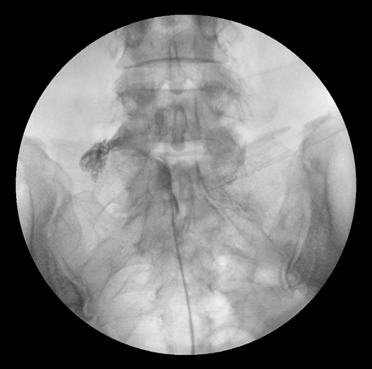

그림4.png 촬영 일시: 2025.04.30

<Fig 2. PEN 시술로 오래된 신경염증 부위에 약물이 정확히 전달 된 모습>

"선생님! 정말 신기해요.

밤에 누워도 다리가 안 저려요!

오른쪽 다리 쥐도 안 나고

찌릿한 것도 거의 없어져서

다시 운동을 가르칠 수 있게 됐어요."